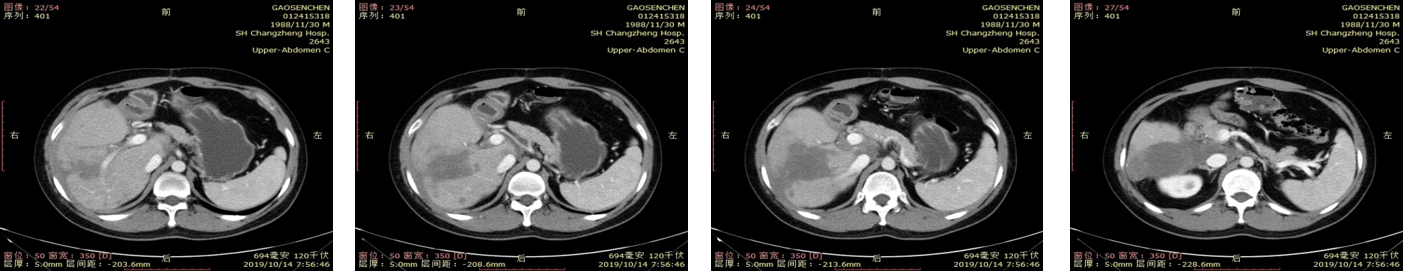

上腹CT 2019-10-24

2019-10-14上腹CT提示肿瘤较前明显退缩。